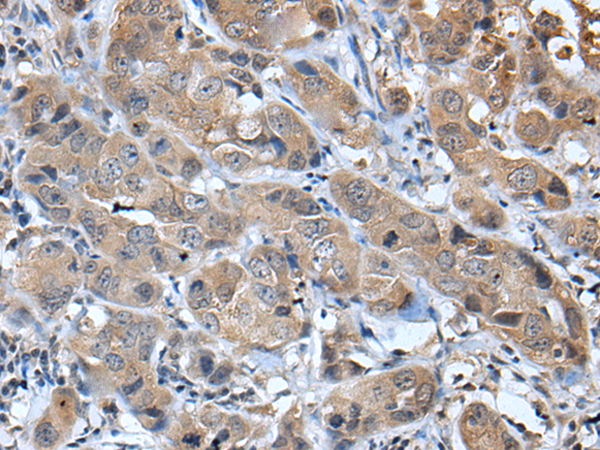

分类: 科研抗体货号: P12729别名: MDGI; FABP11; H-FABP; M-FABP; O-FABP应用: WB,IHC反应种属: Human, Mouse, Rat